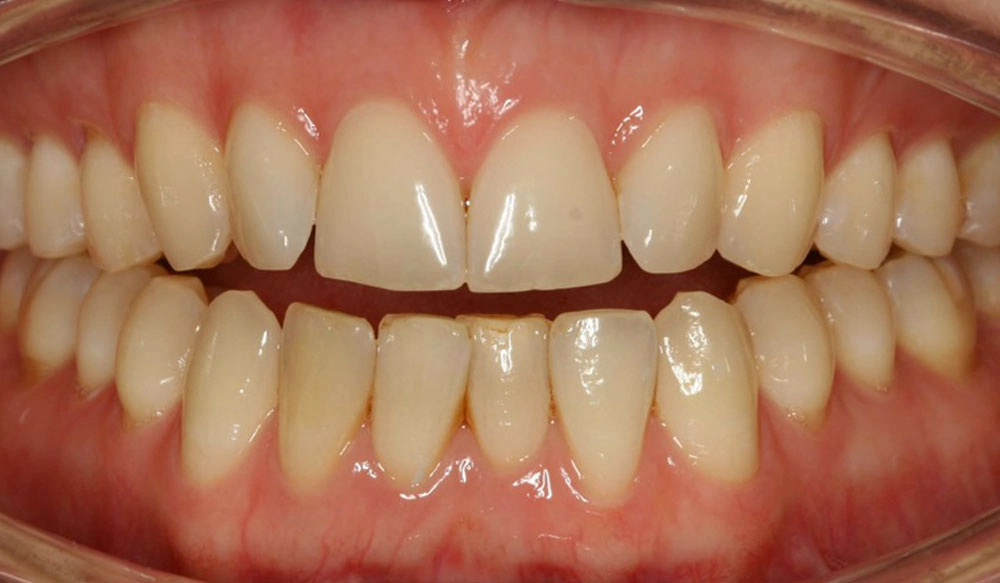

Crowding

Crowding is the condition in which there is a discrepancy between tooth size and space available for the teeth to be aligned in the dental arch

Patient Information:

Age: 17

Gender: female

Invisalign Treatment Option: Invisalign Comprehensive

Total Treatment Time:

29 months